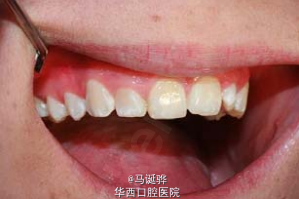

越来越逆天的侧切牙

伴随着越来越多的侧切牙双根管被大家发掘,大家对这个小牙齿是不是有点胸有成竹。但是,道高一尺魔高一丈,侧切牙也越来越不让人省心了。